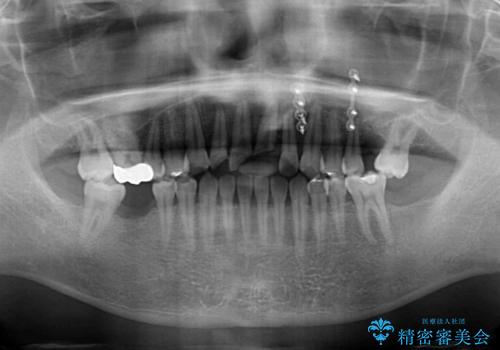

- ソーシャルメディアでのゲームに夢中になっている最中に車と接触し、前歯の抜歯を余儀なくされた患者様です。

初診時では前歯が保存できる可能性も模索しましたが、損傷が激しく3歯を抜去することとなりました。

保存となった隣在歯も神経が失活していており、補綴治療が必要であったので、オールセラミッククラウンにて補綴治療することとしました。

奥歯には元々欠損があり、欠損に伴う咬合不正も認められたため、部分矯正を行った上でインプラント補綴治療も行うこととしました。